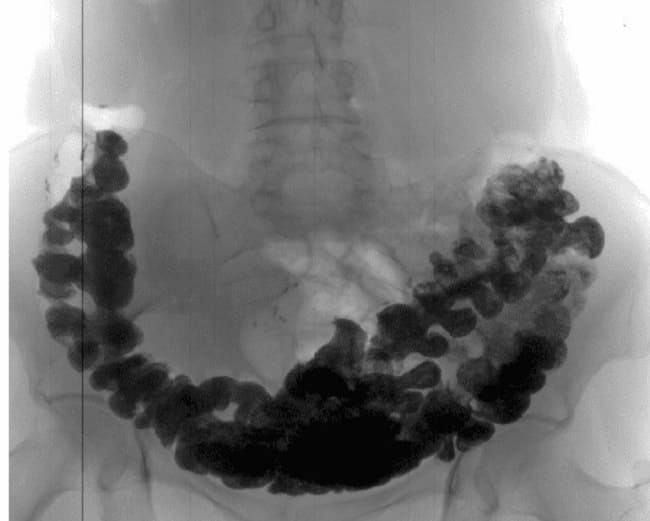

X-rays of callous stones in the colon

Intestinal cancer forms unnoticed for 1-2 years